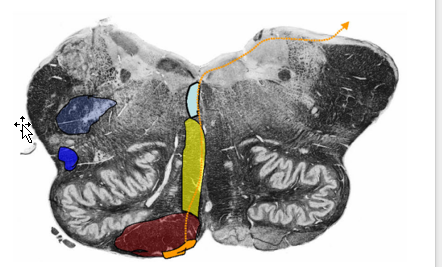

List the three prominent features found at the midolivary level

Prominent Features

Inferior olivary complex

Hypoglossal nerve

exits preolivary sulcus

Vagus nerve

exits postolivary sulcus

Describe the Structures found @ Midolivary Level

Inferior Olivary Complex:

Constituents:

Principle Olivary Nucleus

Function:

Control of planned or skilled voluntary movement

predominantly cortical (and subcortical) afferents

Medial/Dorsal Accessory Olive

Stereotyped Movement

Receives predominantly spinal afferents

inferior cerebellar peduncle (olivocerebellar tract)

inferior olive → cerebellum (contralaterally)

Reciprocally connected